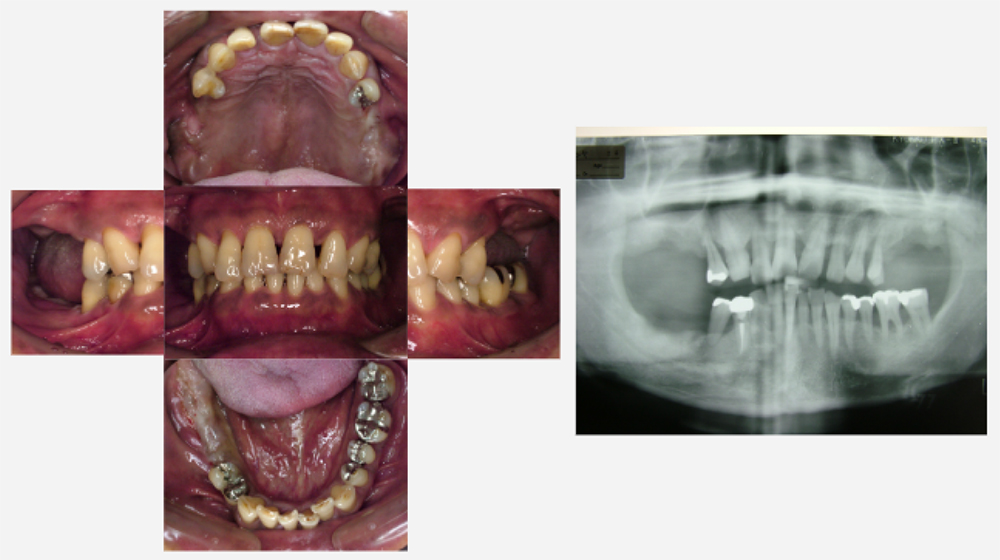

治療前治療後

| 治療内容 | インプラント奥歯1本・根管治療・矯正治療(圧下) |

|---|---|

| 患者様の年齢 | 40歳 |

| 患者様の性別 | 男性 |

| 治療期間 | 1年 |

| 治療回数 | 矯正治療合わせて50回程度 |

| 治療費用 | 根管治療1歯6万円/インプラント治療1歯50万円 矯正治療:1歯 10万円 |

| 治療で得られるメリット |

|

| 治療する際に起こる リスク・副作用 |